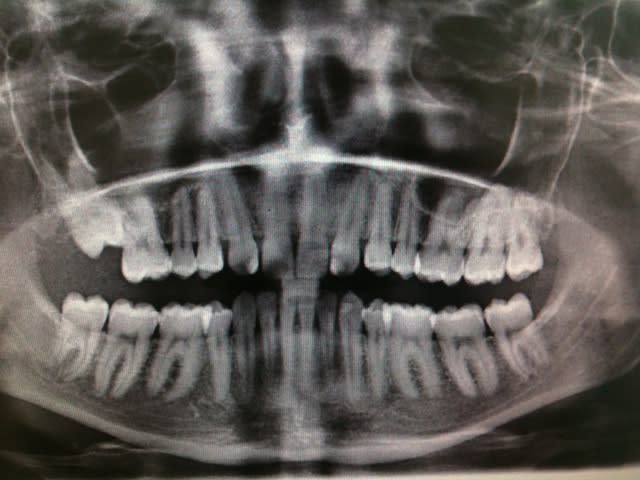

Question subsidiaire tant que je vous tiens, la pano concerne une jeune fille de 21ans qui a été traitée dans un service d'odf, ils n'ont pas touché à la 17, qu'en pensez vous?

Ca se tente d'aller la chercher? Sachant qu'il faudra lui faire faire une rotation?

2eme cas: ha bon, elle a suivi une traitement ODF????? Du coup occlusion est bof, il lui manque 4 dents et une cinquième est pas sur l'arcade, que du bonheur!

Je reviens sur la pano....

T'as un historique afin de savoir pourquoi il manque 12 et 22? Savoir si il y eu des soucis durant le traitement? Genre elle était pas très souvent à ses rdv ou si "tout s'est bien passé" selon son ortho?

La courbe oclusale est tout sauf une courbe mais une suite de vallons et de monts, y'a des diastèmes, des axes pas droits, des rotations.... à droite je me demande presque si c'est pas un 8 celle qui est incluse.... Planas doit s'en retourner dans sa tombe!

Jolie panique à n'attaquer que si la patiente est sérieuse.

Pour le second cas c'est une patiente très sérieuse qui était suivie en odf dans une Fac, elle m'a dis être née avec 4 canines en haut mais je penche plutôt pour une agénésie des 2.

Pour la 17 elle m'a dis qu'ils lui ont proposé d'aller la chercher mais elle n'a pas voulu (ça m'étonne que ça n'a pas été une condition sine qua none pour engager le traitement). Tu penses que c'est jouable d'aller la chercher? Je ne l'ai pas adressée elle.

Aucun problème pour aller chercher la 17, si elle n'est pas ankylosé bien sur.

Dans l'absolue il n'y pas besoin de minivisse, mais vue l'age de la patient ca lui évite d'avoir a porter un appareillage fixe.